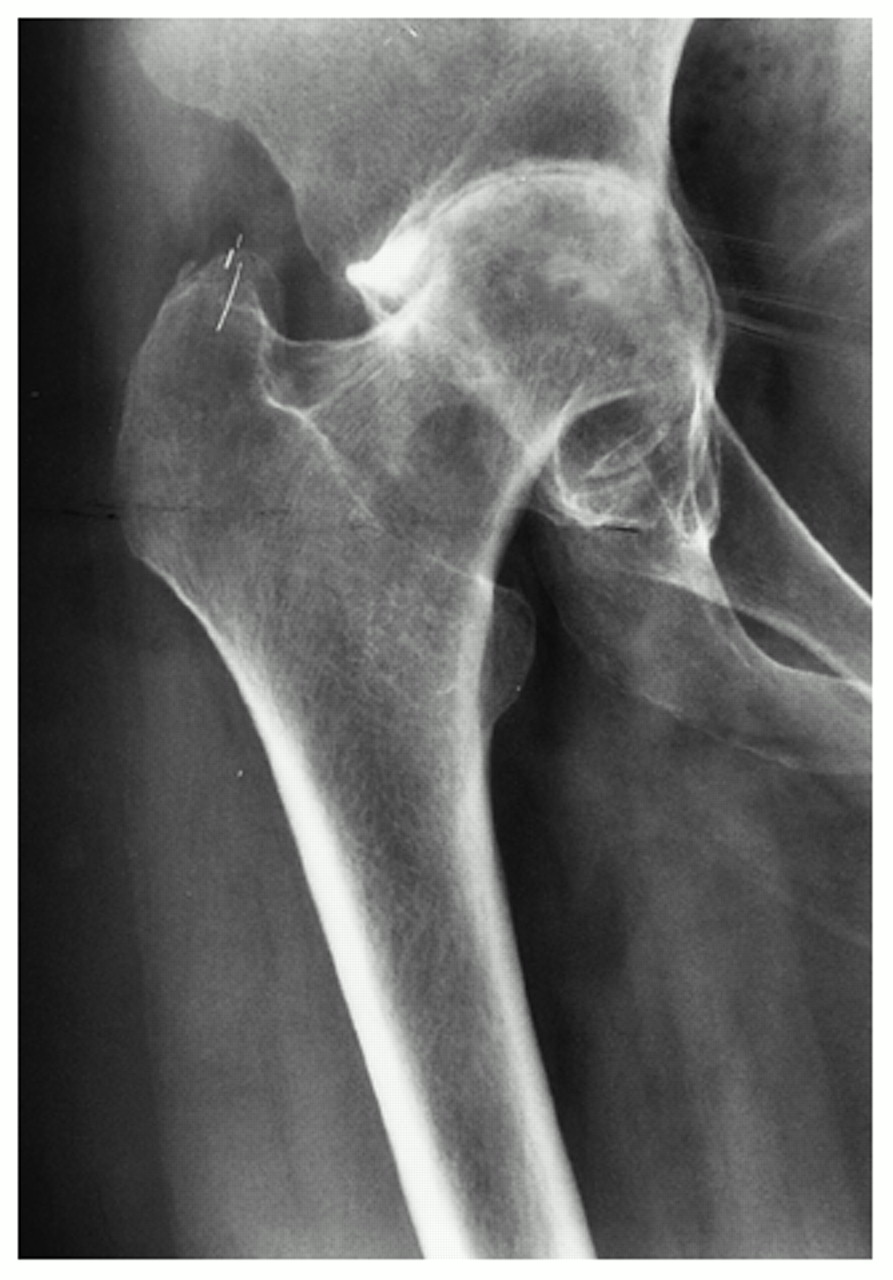

Rheumatic arthritis causes joint erosion and joint destruction visible on x-rays and symptoms that can be severe and limiting. As the joint becomes eroded the cartilage is damaged and the articulation of bone-on-bone causes severe pain. Damage to cartilage, tendons, ligaments and bone causes the hip joint to become deformed and even unstable as rheumatoid arthritis progresses.

The frequency of acetabular protrusio is higher in rheumatoid hips as is the likelihood of significant femoral head deformity. Bone quality is poor especially in those patients who have needed long term steroid treatment. This makes these operations more difficult, with a higher risk of per-operative and post-operative complications.

Infection is slightly more common in patients with rheumatoid arthritis, partly due to the disease and partly due to the drugs used for treatment. As the soft tissues are affected by the rheumatoid process the risk of post-operative limp is higher, along with the rate of hip dislocation.